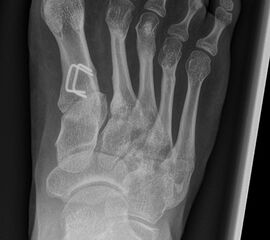

In der Regel bestehen aktive Wachstumsfugen bei Mädchen bis zum 12. und bei Jungen bis zum 14. Lebensjahr, mit Abweichungen von einem Jahr nach unten und nach oben. Präzise Informationen unter anderem darüber gibt das präoperative Röntgenbild (Abb. 2).

Abb. 2 a-c: offene Wachstumsfugen MT I Basis und Zehen (a), teilweise geöffnete Wachstumsfugen (b) und geschlossene Wachstumsfugen (c).

Zum Lesen der Bildbeschreibung und zur Vollansicht bitte die Bilder anklicken. Bilder: A. Helmers.